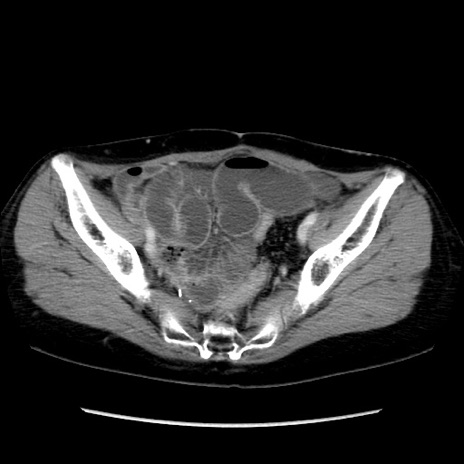

症例32(横断像)

【症例】40歳代 女性

【主訴】上腹部痛、嘔気・嘔吐

【現病歴】約9時間前頃から急に上腹部痛、嘔気、嘔吐が出現。改善しないため救急要請。

【既往歴】子宮頚癌(広汎子宮全摘術、放射線療法)、腸閉塞

【身体所見】腹部:平坦、軟、腸雑音亢進、上腹部を中心に腹部全体に圧痛あり。

【データ】WBC 8400、CRP 0.03